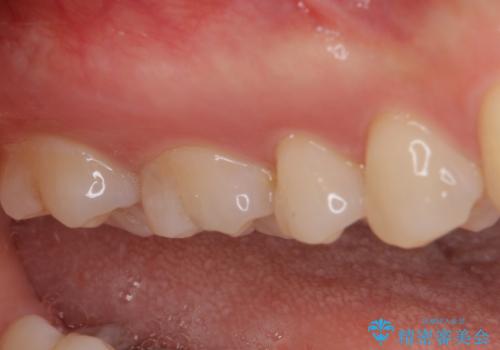

セラミックとゴールド 奥歯のむし歯治療

下顎は口を開けたときに目立つためセラミックインレーに、上顎奥歯は機能面を優先してゴールドインレーにて修復治療を行うこととしました。

機能面を優先すると、PGAインレー(ゴールドインレー)による修復治療やPGAクラウンによる補綴治療が望ましいのですが、笑ったときに見えている銀歯がどうしても気なってしまうとのことで、目立ってしまう奥歯はセラミックインレーやセラミッククラウンを装着することとしました。

見た目を気にすることなくむし歯治療を行うことができ、患者様に大変満足していただきました。